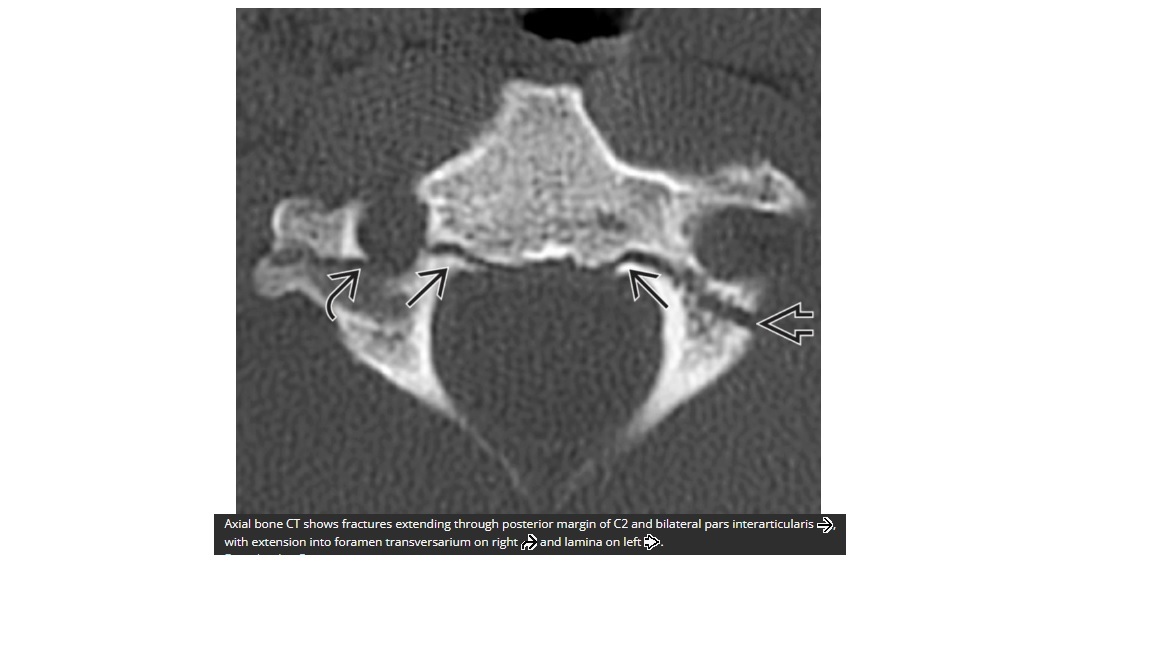

What is hangmans fracture?

A

Bilateral pedicles or pars fracture of C2

Anterior subluxation of the C2 body, canal widening so cord damage uncommon

associated avulsion fracture of the Anterio inferior corner of C2 (ALL)